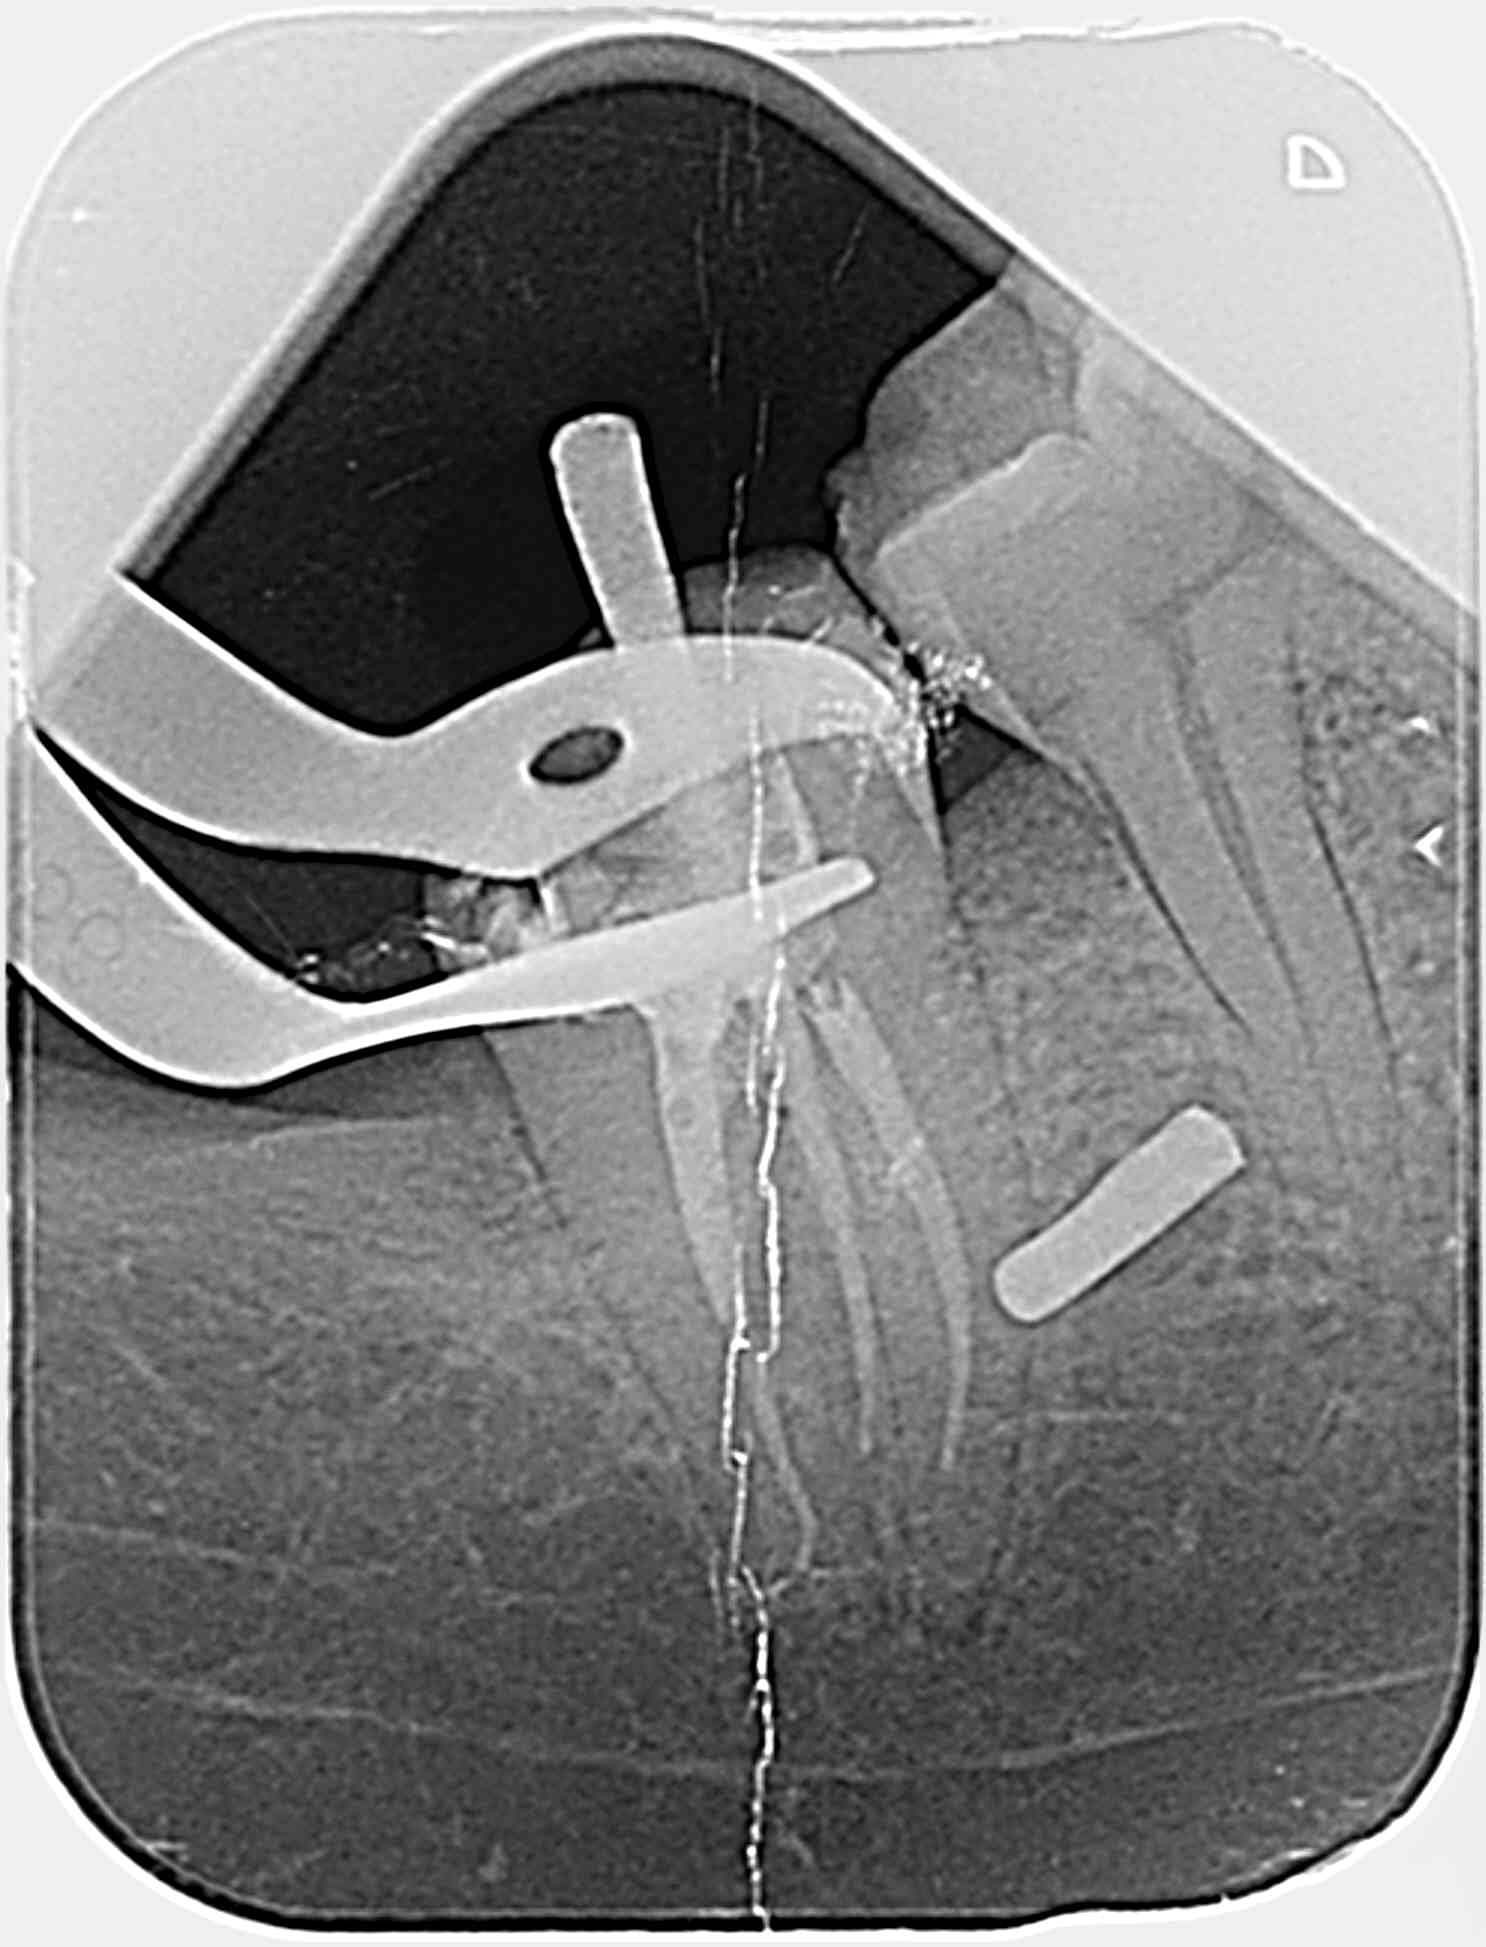

Je fais une radio per-op avec deux cônes de gutta fins de diamètre 20 4% dans les deux canaux mésiaux et … surprise…

Qu'en pensez-vous ?

1/Mon ML correspond a un canal secondaire qui va du plancher pulpaire vers l'espace interdentaire ? Ou bien ML dans racine que je ne vois pas (je ferai des radios excentré prochaine fois)?

2/Comment obturer si petit canal secondaire vers espace interradiculaire ? gutta? MTA ?

merci pour vos réponses, Pour la perf, je ne pense pas… D'ailleurs sur la pré-op on semble voir quelque chose à l'endroit de ma future pseudo perf..?

@bagheerra : J'ai édité mon message puisque je me suis trompé dans ma question 1/, je parlais du ML et non du DV. Les deux cônes sont dans les mesiaux comme indiqué.

Je suis assez sur que ce n'ai pas une perf, donc si localisateur sonne tôt, canal secondaire partant de la chambre vers espace inter radiculaire ? Dans ce cas la je n'ai que deux canaux, un MV et un Distal excentré en vestibulaire.

Si je regarde le plancher de la chambre pulpaire (couple transversale), mon C est relativement peu bombé en forme et va du MV classique au distal excentré en vestibulaire. Le dos du C est vers vestibulaire. N'es-ce pas curieux au vu de la radio pre-op ou l'on voit deux racines mesiale et distal séparées ? Ou bien le C est vraiment très peu profond comme j'en ai l'impression.

Bon après lecture des réponses et réflexion, j'opte (j'espère); soit, le moins probable, pour un canal secondaire de la chambre vers l'espace inter radiculaire, soit, le plus probable pour une anatomie en C donnant l'impression que mon MV est en inter radiculaire (type TIB postée par BURNAX).

Je vais tabler sur une morphologie en c (5 à 7% des 2e molaires mandibulaires) et une imagerie à la "burnax". Le plancher pulpaire ressemble au cas posté par Bill. Un c vestibulaire de distal à mv et un canal individualisé en ml. Dans ce cas le mv peut apparaître dans la furcation à la radio...